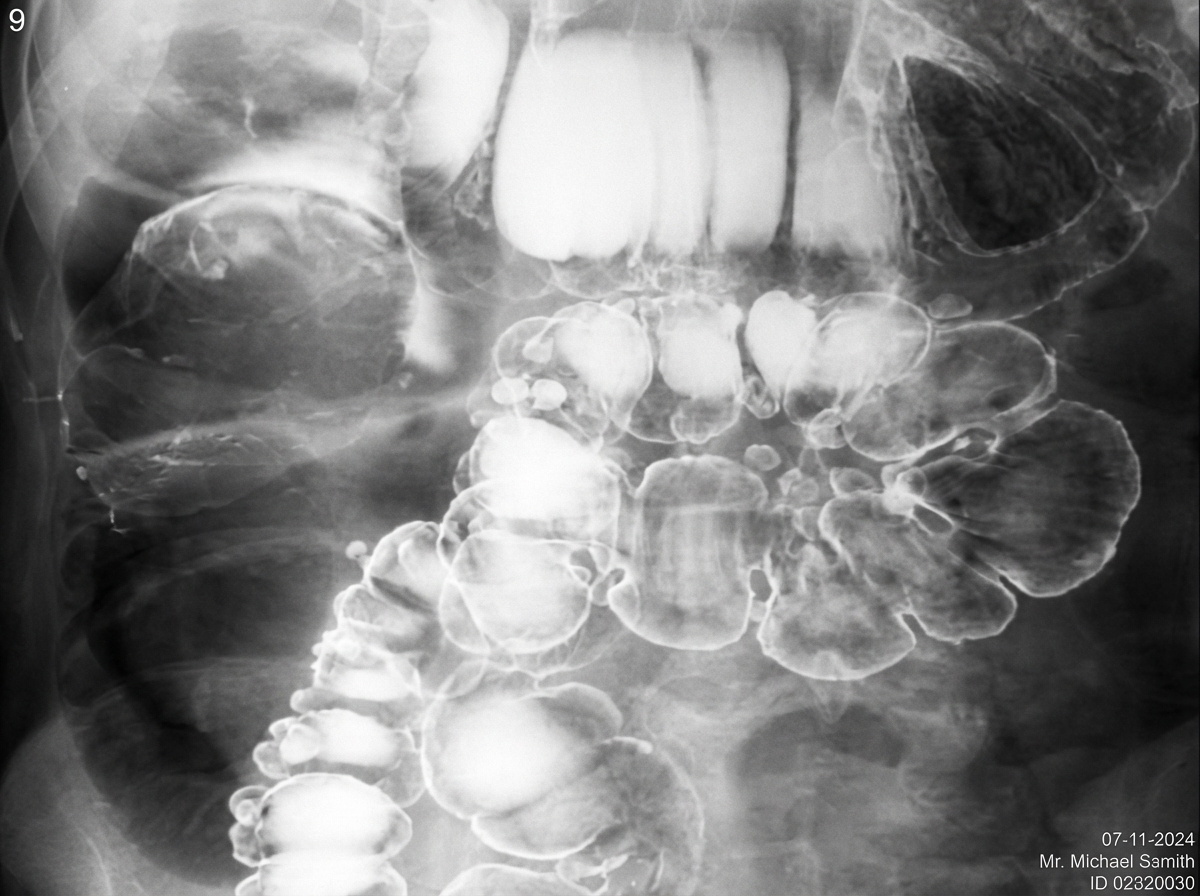

What condition is suggested by the following appearance on a barium enema?

Explanation: ***Intussusception*** - Classic **coiled spring sign** or **claw sign** on barium enema due to the telescoping of bowel segments creating a characteristic appearance. - **Meniscus sign** may also be present, representing the leading edge of the intussuscepted bowel outlined by contrast. *Ulcer* - Presents as a **crater-like defect** with contrast collection in the ulcer base, not a telescoping appearance. - Usually shows **mucosal irregularity** and inflammation around the defect rather than the smooth, rounded contours of intussusception. *Carcinoma* - Appears as an **irregular filling defect** with **apple core sign** showing luminal narrowing and shouldering. - Demonstrates **mucosal destruction** and rigid bowel walls, contrasting with the smooth, mobile appearance of intussusception. *Diverticulum* - Shows as **outpouchings** or **sac-like projections** extending beyond the normal bowel contour. - Appears as **contrast-filled pouches** communicating with the bowel lumen, completely different from the telescoping pattern of intussusception.